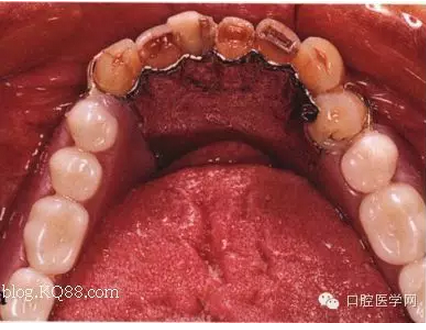

先注明一下:本文圖片部分來自李望松的支架設(shè)計圖譜收集u/210/archives/2008/25181.html,借圖表達一下,沒有別的目的,只是讓文章更生動些,李老師一直是我崇拜的偶像,只是近來很少見到他的文章,期待李老師的大作,言歸正傳——————修復大夫要精通支架設(shè)計,作為一個修復大夫,是第一個獲得患者牙體狀況的,所以說在哪放個合支拖,在哪放個卡換,至關(guān)重要,因為我們做的是個有創(chuàng)不可逆操作,既要兼顧牙周狀況,又要兼顧粘膜狀況,以及牙槽脊的情況,所以說當給患者做完檢查以后我們頭腦中就應該有一個大體支架了,以前,總是太依賴加工廠了,取完模剩下的好像都是交給了加工廠了,怎么設(shè)計,你看摸著辦吧,仿佛設(shè)計那是加工廠的事,可是做了幾回再加上自己的學習,經(jīng)驗,加工廠的設(shè)計總是不怎么樣,以前設(shè)計的方案仿佛根深蒂固,一直就認為那是正確的就那么設(shè)計,再加上以前看過支抗兄的一篇文章,也是深有感觸,一個不科學的設(shè)計方案,那樣就成了一個慢性拔牙器。看看幾幅圖片

看紅箭頭處為什么要空出一點距離?,看看自己加工廠設(shè)計的不管牙怎樣是不是都成了一個整體呢?對于愕板或者是

愕桿要離開齦緣4-6mm,以促進食物對牙齦的按摩沖刷作用,促進牙齦健康